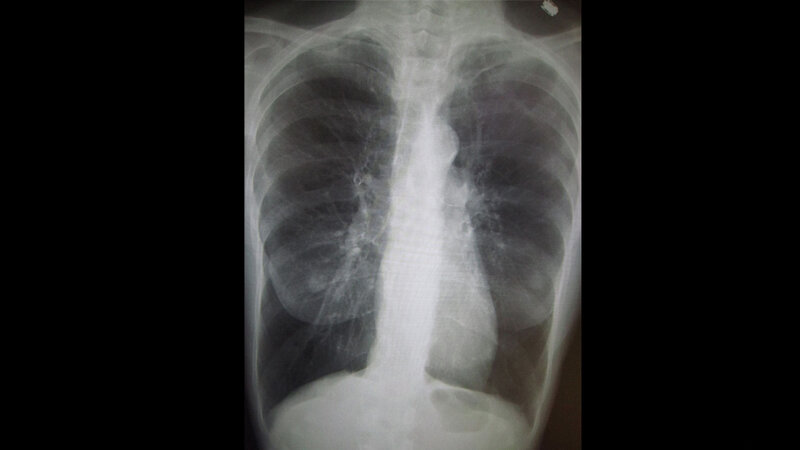

Patienten mit schwerer Atemnot leiden in der Regel unter einer ernsthaften Lungenerkrankung, zum Beispiel COPD, Lungenfibrose oder Lungenhochdruck. Vor allem die Zahl der Menschen mit COPD hat in den vergangenen Jahren stark zugenommen. Ein Ende dieser Entwicklung ist bislang nicht absehbar. Am Programm BETTER-B (BETter TrEatments for Refractory and chronic Breathlessness) beteiligen sich Einrichtungen aus mehreren europäischen Kliniken, in denen Patienten mit schwerer Atemnot behandelt werden. Das Projekt hat mehrere Komponenten. Um zum Beispiel ein Bild der aktuellen Behandlungspraxis zu bekommen, befragen die Experten Ärzte über ihr übliches Vorgehen und wie sie bestehende Richtlinien nutzen.